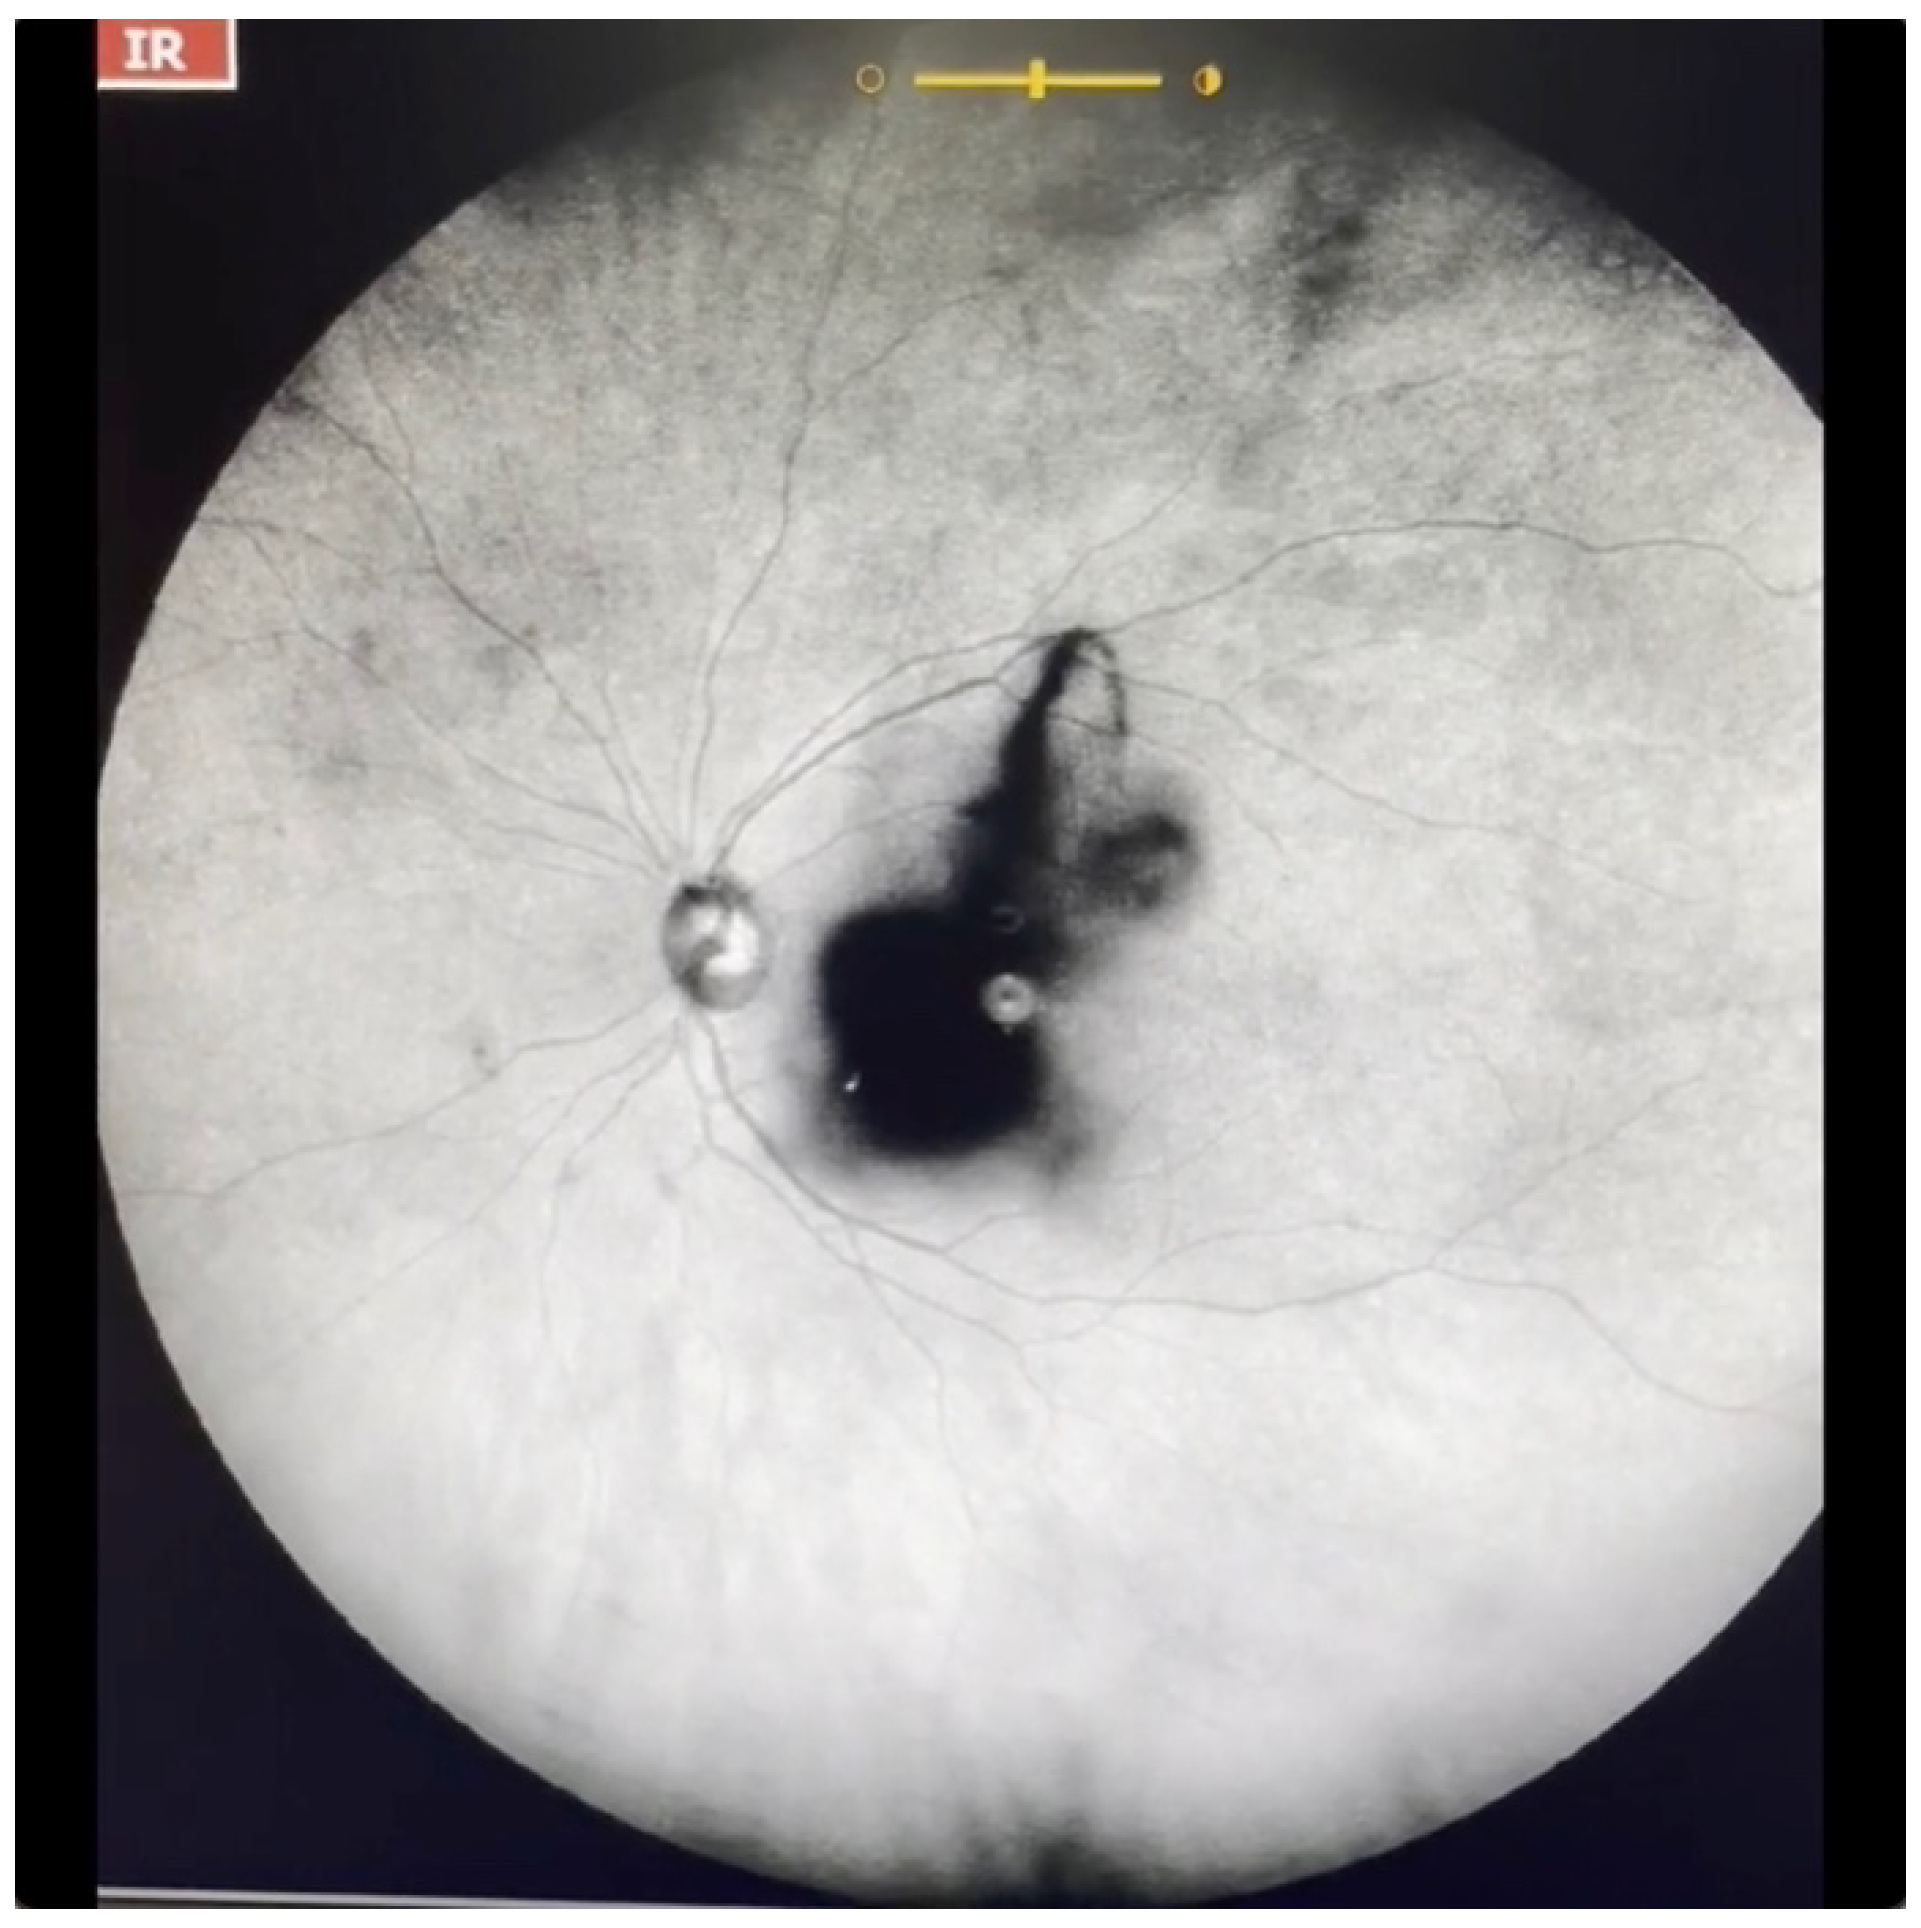

Figure 7.

Ultra-widefield IRcSLO image of an eye with Grade 5 vitreous floaters secondary to posterior vitreous detachment. A very dense shadow is observed inside the macular area. See also Video S7.